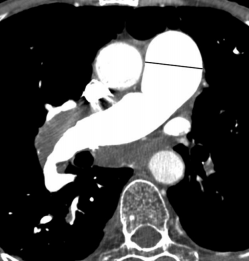

Signes de Surcharge

- Rapport VD/VG inversé (supérieur à 1)

- Inversion du septum interventriculaire

- Dilatation du tronc pulmonaire (rapport TP/AA >1)